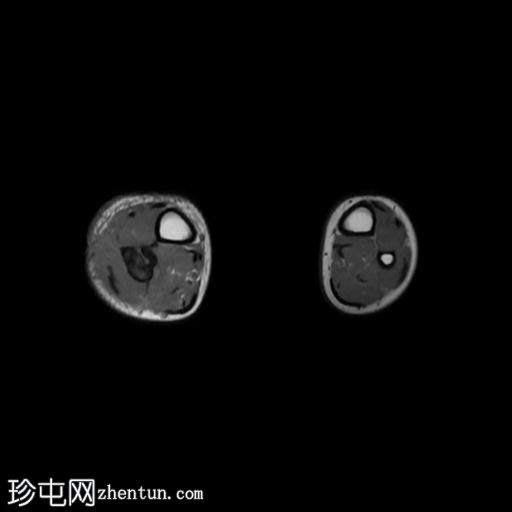

轴位

STIR序列

腓骨可见广泛的骨髓水肿,伴有明显的皮质和骨膜增厚,整个腓骨均呈高信号。腓骨外侧中下三分之一交界处可见局灶性皮质破坏,并可见一条高信号瘘管延伸至周围皮肤。

此外,软组织(包括肌肉和皮下组织)也受累。